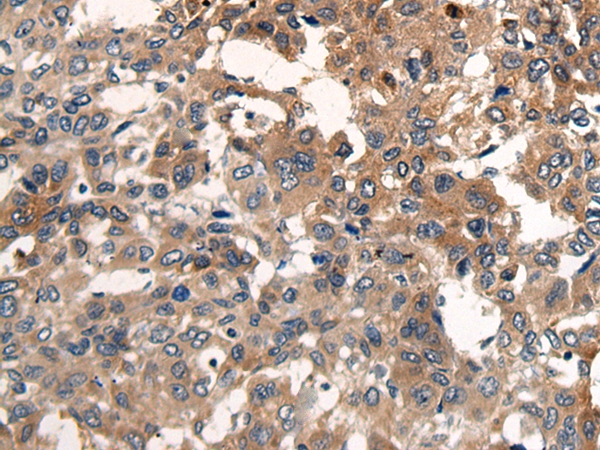

The image on the left is immunohistochemistry of paraffin-embedded Human liver cancer tissue using 46450(CDH17 Antibody) at dilution 1/35, on the right is treated with synthetic peptide. (Original magnification: x200)